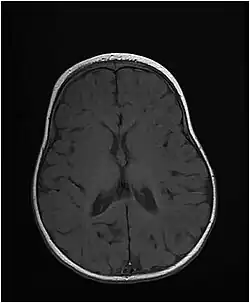

| Axial T1-weighted MRI of the brain at 10 months old showing under-myelination of the internal capsules, relative under-myelination of the remainder of the subcortical white matter, and a thin corpus callosum. From an MTHFS deficiency case report by Romero et al., 2019.[1] | |

The disease starts at birth or in early infancy and presents with microcephaly, short stature, and developmental delay. Patients develop seizures that may be hard to control. Brain imaging shows delayed myelination and hypomyelination.[2] Mutations of the MTHFS gene disrupt folate metabolism, which is very important for the proper development of the nervous system and myelination of nerve fibers.[2]